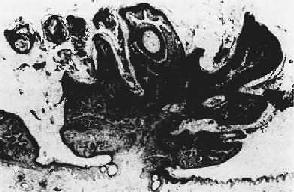

一、良性上皮组织肿瘤1.乳头状瘤(papilloma)由覆盖上皮发生,向表面呈外生性生长,形成许多手指样或乳头状突起,并可呈菜花状或绒毛状外观。肿瘤的根部常较狭窄成蒂与正常组织相连。镜下,每一乳头由具有血管的分支状结缔组织间质构成其轴心,其表面覆盖的增生上皮因起源部位不同而异,可为鳞状上皮(图7-9)、柱状上皮或移行上皮。在外耳道、阻茎及膀胱和结肠的乳头状瘤较易发生恶变而形成乳头状癌,值得注意。

图7-9 皮肤乳头状瘤 2.腺瘤(adenoma)是由腺上皮发生的良性肿瘤,多见于甲状腺、卵巢、乳腺、涎腺和肠等处。粘膜腺的腺瘤多呈息肉状(图7-10),腺器官内的腺瘤则多呈结节状,且常有包膜,与周围正常组织分界清楚。腺瘤的腺体与其起源腺体不仅在结构上十分相似,而且常具有一定的分泌功能。不同这外仅在于腺瘤的腺体大小、形态较不规则,排列也比较密集。发生于有小叶和导管结构的器官的腺瘤,其小叶结构往往缺如或不明显,亦无导管形成,故不能将其分泌物排出。